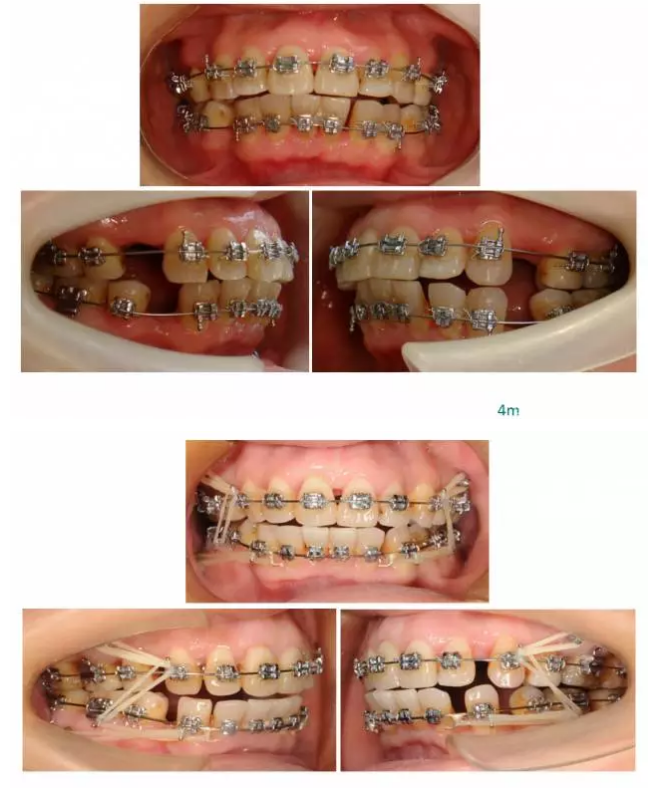

【原創(chuàng)博客】這樣的代償矯治大家滿意嗎?(重度骨性二類)——侯志明

QQ圖片20150824150825.png

QQ圖片20150824150547.png